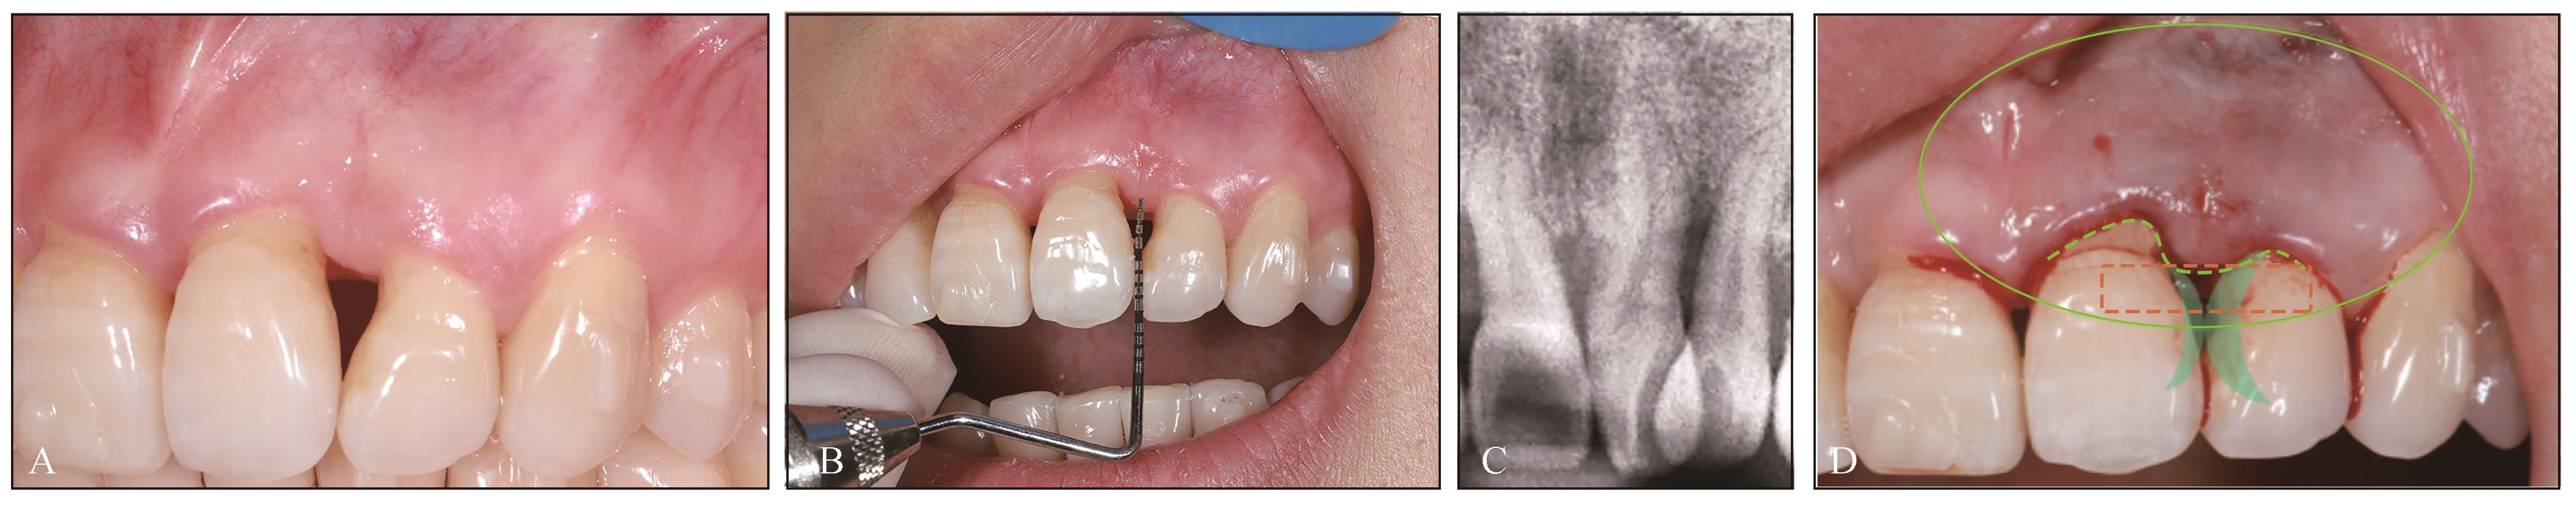

图 3

术前检查及治疗设计A:唇侧观;B:术前测量;C:X线片;D:术前设计,21、22牙间沟内切口及靠腭侧分离唇侧龈乳头(绿色虚线示),唇侧瓣通过隧道技术冠向复位(绿色椭圆型区域),接触点下降的范围(橙色虚线示),牙冠通过贴面修复(绿色半月形示)。"